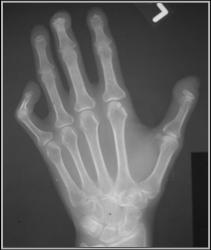

Scleroderma